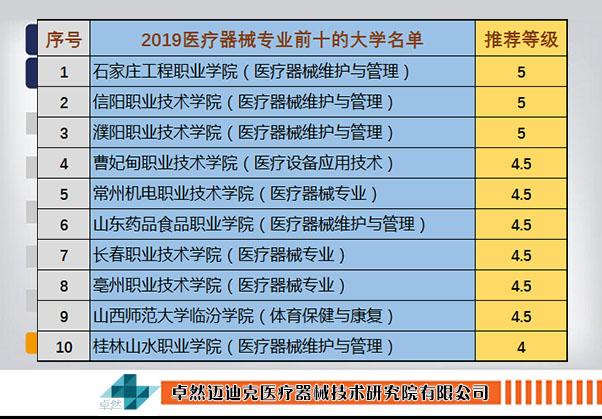

医疗器械 关节置换手术 附2019年医疗专业大学排行榜